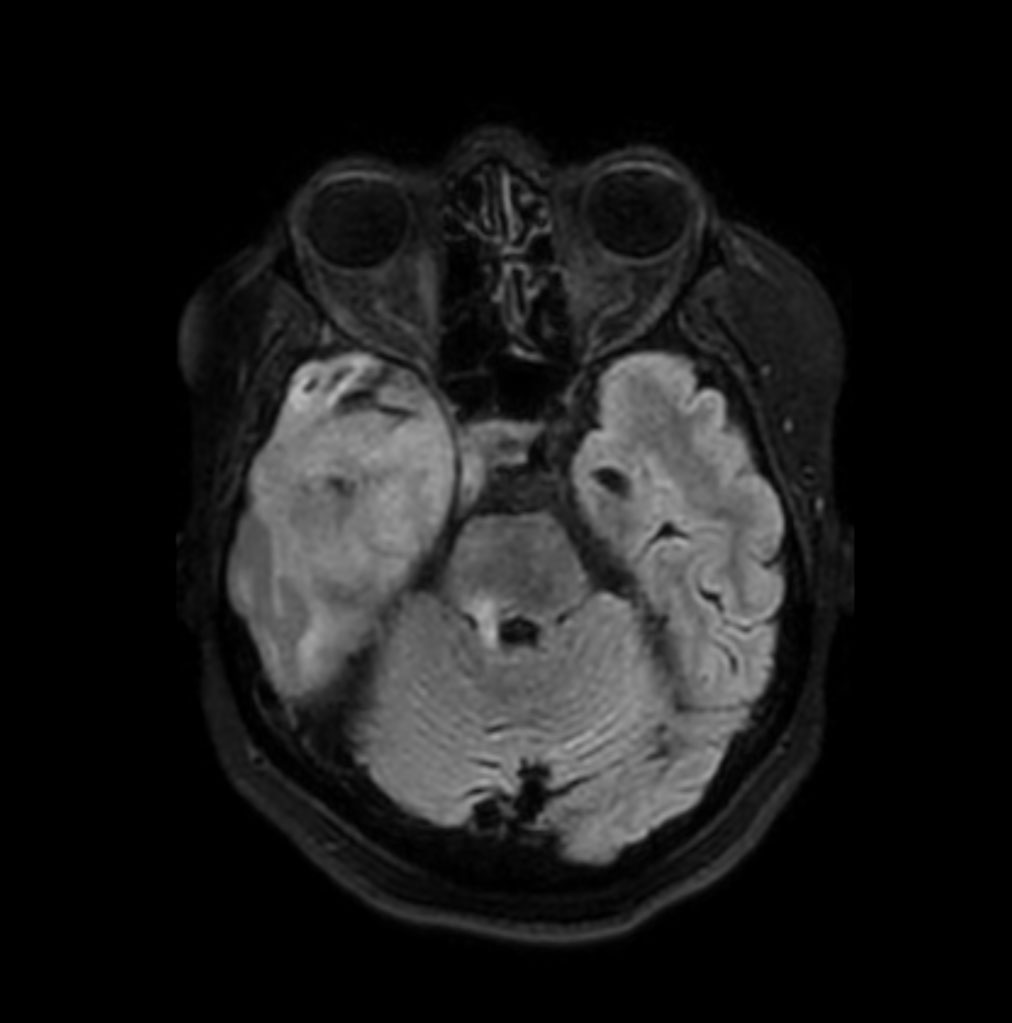

Axial DWI (b1000)

-